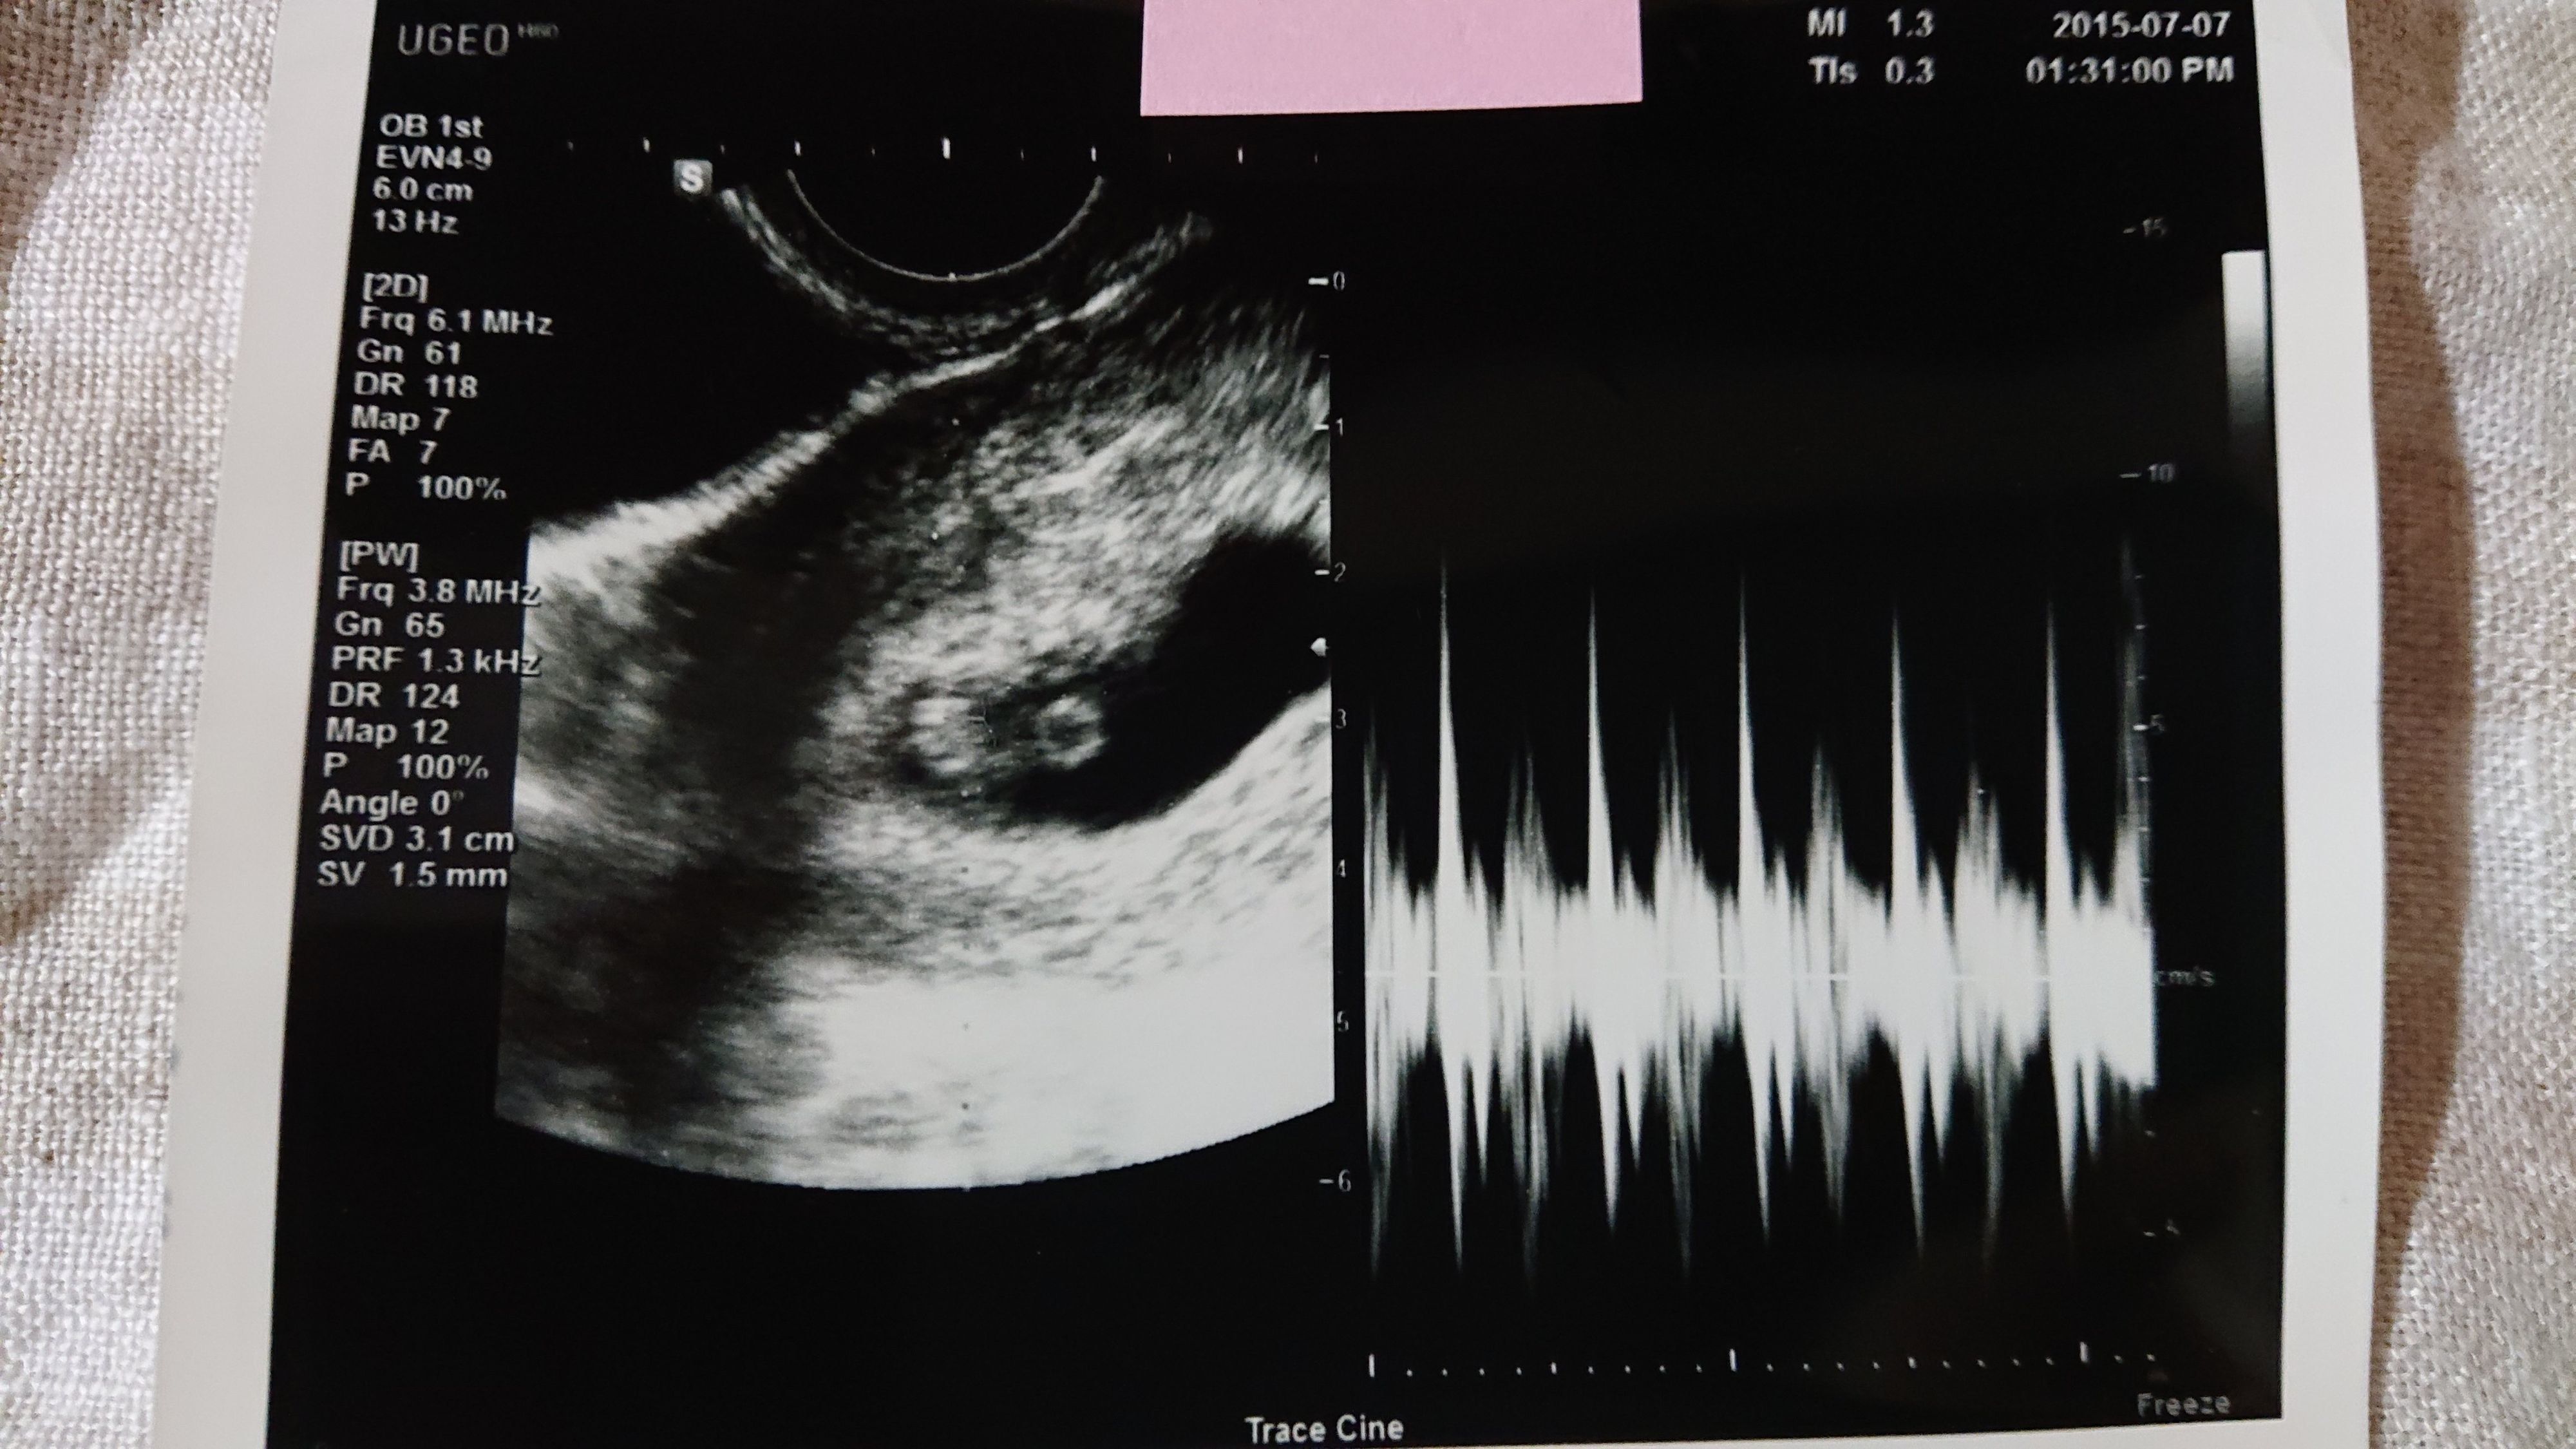

《妊娠7週目のエコー写真》

妊娠7週目の健診日には、午前中に夫と一緒に市役所へ婚姻届けを提出し、母子手帳も発行してもらいました。夫は車酔いをして具合が悪くなってしまったので、健診の時は夫には留守番をしてもらい、もらいたてホヤホヤの母子手帳を手に、1人でドキドキしながら産婦人科へ行きました。すると、胎嚢の中に赤ちゃんの姿が…!「やっと会えたね~」と、嬉しすぎて食い入るように見ていたエコーの画面。「もっともっと長く見ていたい」と切に願ったほど感激しました。そして、この日は同時に心拍も確認でき、心臓も元気に動いていました。2枚目のエコー写真の右側半分が、心拍を確認できた証拠です。医師からは「小さすぎて予定日はまだ決められないな~。でも、3月上旬ぐらいになるかな~」と伝えられ、予定日確定は次回持ち越しに。夫は「成長遅いんじゃない?」と心配そうにしていました。翌日には、私たちの結婚式が控えていました。その前に赤ちゃんの姿を見つけることができたおかげで、遠方の両親にも直接妊娠報告することができて嬉しかったです。